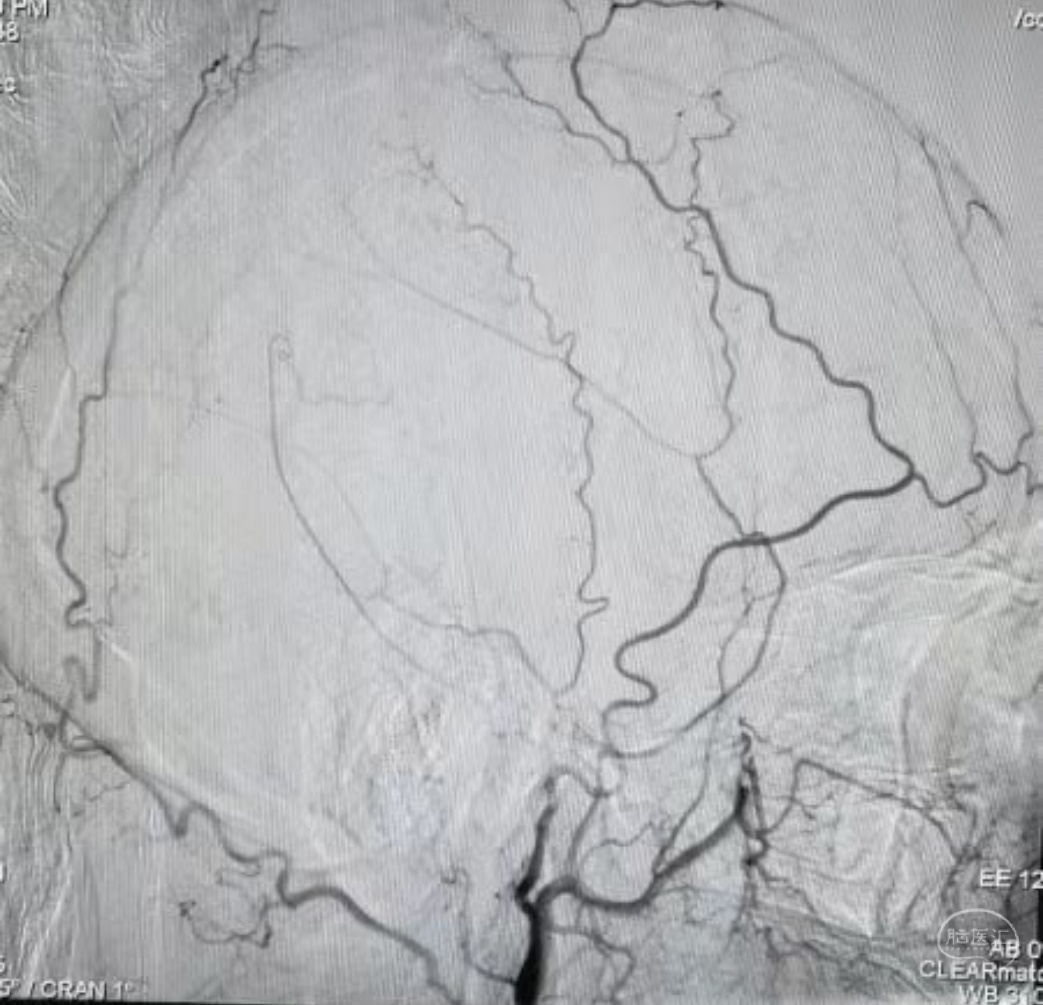

DSA示:左侧大脑中动脉闭塞,烟雾样血管形成。

DSA示颞浅A未向颅内代偿。

DSA示:左侧大脑前、大脑中动脉闭塞,烟雾样血管形成。